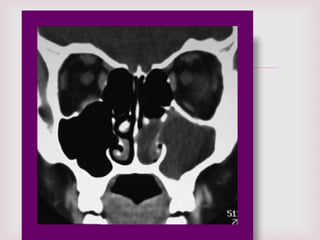

EXÁMENES RADIOGRÁFICO

RX SENOS PARANASALES

De poca ayuda en el dx de pólipos

nasales altos falsos positivos y falsos

negativos.

TUMOGRAFIA COMPUTADA TC

Para confirmar localización y

extensión de la lesión. De gran

utilidad permite planear tipo de

cirugía y evitar complicaciones .